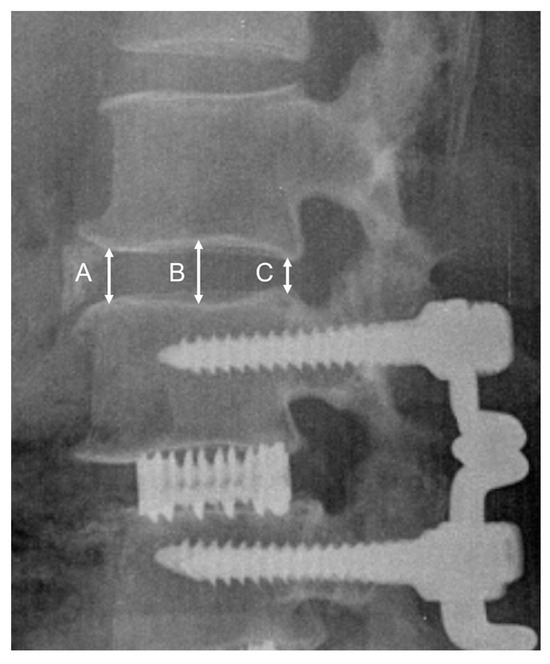

2.2. Surgical Procedure